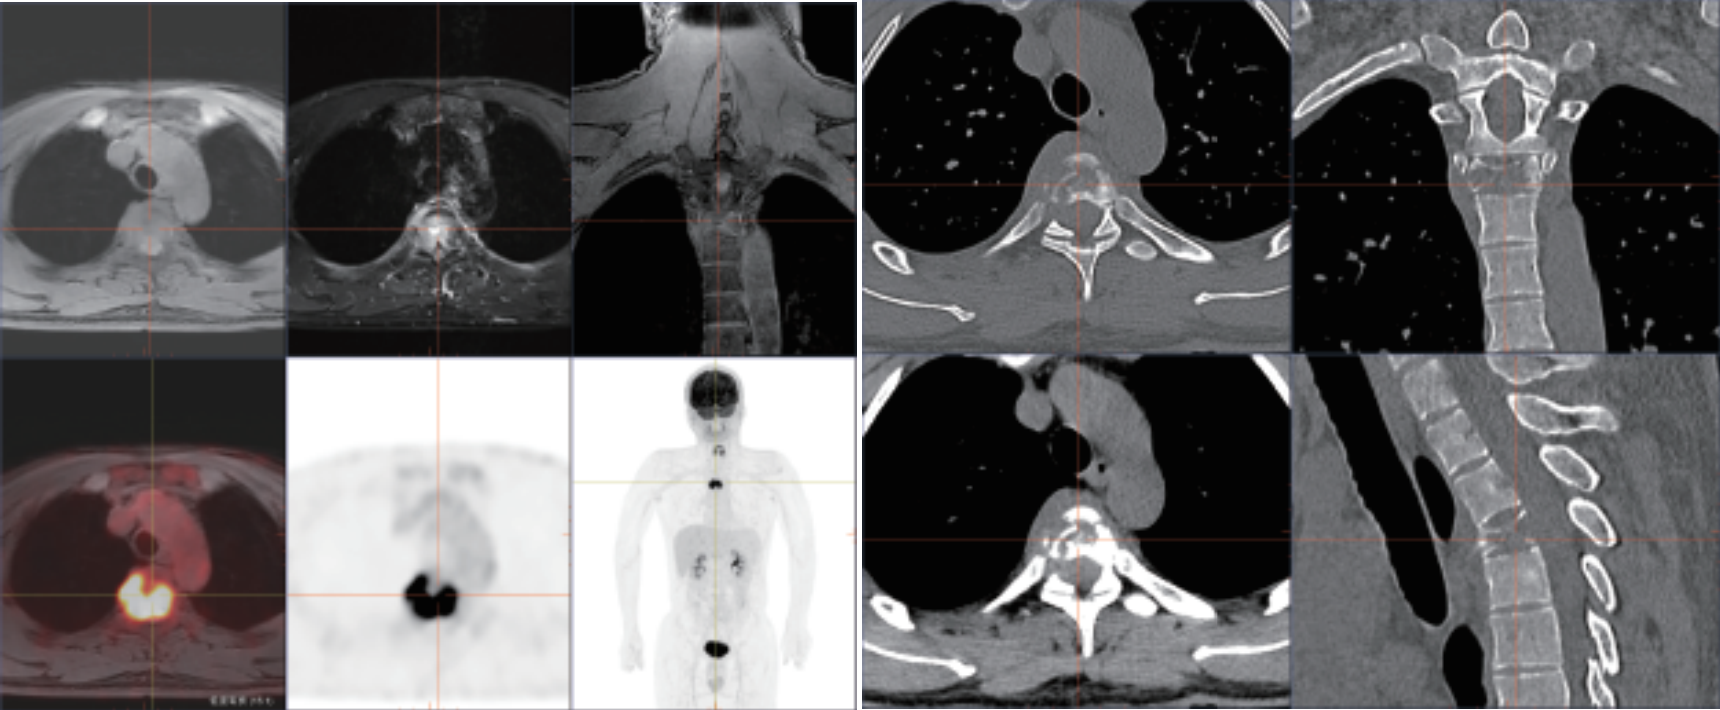

PET/MR是PET和MRI兩者融合的新型影像設(shè)備,其臨床應(yīng)用具有劃時(shí)代的意義。PET/MR在腦、頭頸部、腹腔、盆腔臟器診斷效能具有明顯優(yōu)勢(shì),廣泛應(yīng)用于神經(jīng)系統(tǒng)、頭頸部、胸部、乳腺、肝膽 胰脾、結(jié)直腸、生殖系統(tǒng)、血液系統(tǒng)、骨關(guān)節(jié)系統(tǒng)、不明原因原發(fā)灶腫瘤治療 前檢查、不明原因發(fā)熱、感染和嚴(yán)重性疾病的診療指導(dǎo)以及兒童淋巴瘤、骨肉瘤、神經(jīng)母細(xì)胞瘤分期和療效評(píng)估、復(fù)發(fā)監(jiān)測(cè)和再分期。

? 強(qiáng)大的查體功能:PET和MRI同步掃描,MR 圖像可實(shí)現(xiàn)任意角度的重建和融合, 多角度的觀察解剖和代謝信息,多維度與 PET 實(shí)現(xiàn)軸、冠、矢三維圖像精確融合, 一次檢查便可篩查全身危險(xiǎn)病灶,帶來(lái)更好的科研體驗(yàn)。

? 小病灶高精度成像:TOF飛行時(shí)間技術(shù)精確定位真符合時(shí)間發(fā)生位置,顯著提升圖像對(duì)比度和信噪比,提供更為優(yōu)質(zhì)的臨床圖像,結(jié)合3D光梭成像,可精準(zhǔn)檢測(cè)組織微小病變,為診斷提供更為多元和準(zhǔn)確依據(jù)。

相關(guān)病例成像圖